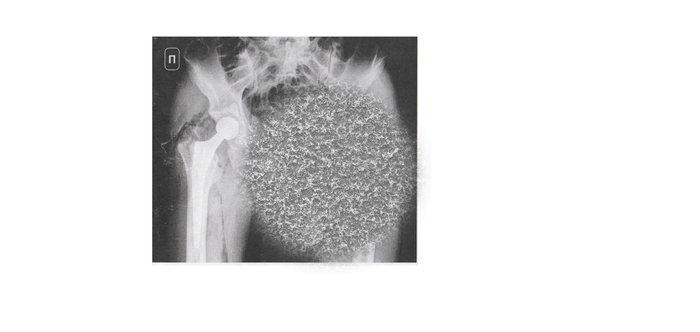

17 марта ложусь в поликлинику и 18 марта по плану мне ставят протез.

Сам протез после операции.